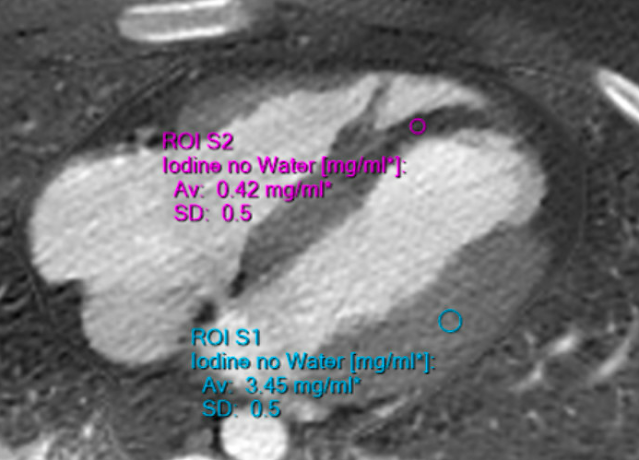

Let's look at a closer view, and also made easier to see using Spectral CT:

The very dark area at the septum and the apex of both ventricles is transmural ischemia. There is no contrast making it into this area which should be perfused by the LAD.

Notice the extremely dark area at the apex and apical part of the septum.